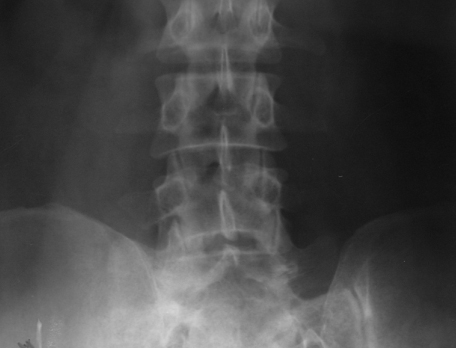

Figure 6: Multiple Myeloma – (a) Diffuse osteopenia with loss of trabeculae, (b) lytic lesions in the bodies.

Figure 7: (a,b,c) Multiple myeloma with osteopenia and early collapse of vertebral bodies BC MRI of the same patient. (d) plain films, (e, f) MRI.